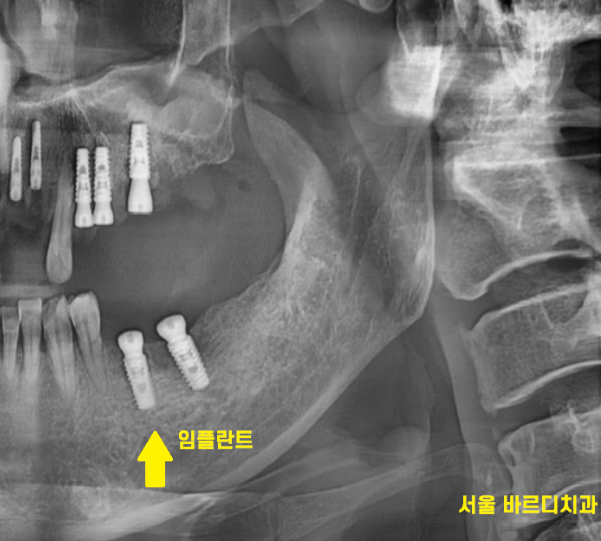

뼈가 거의 없는 경우에는

임플란트를 잇몸 안에 묻어두기도 하는데요.

이럴 경우에는 잇몸밖에 안느껴지기 때문에

임플란트 심은게 맞나.. 싶기도 합니다.

230707

겉으로 봤을 때는 잇몸만 느껴지지만

x-ray를 보실까요~?

230717

임플란트가 잘 심어져있습니다.

이럴 경우 잇몸 밖으로 나사를 연결하는

2차 수술을 진행해야 하는데..